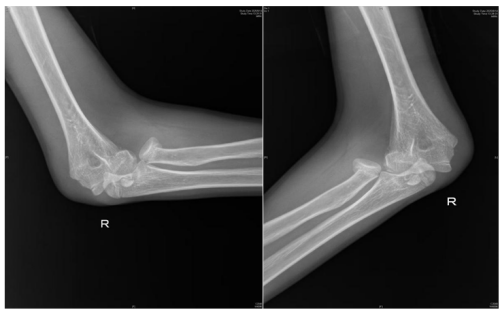

近日,13岁的邓佑(化名)在放学途中,一边看手机一边走路,未留意前方障碍,整个人猛地撞上了护栏,在倒地的瞬间,他用右手撑地,随即感到一阵钻心的剧痛从肘部爆发开来,被紧急送往91短视频 (南华大学附属长沙中心医院)手足显微外科就诊。经系统检查,被诊断为:右桡骨头骨折、肱骨内上髁骨折、右肘关节脱位。

“患者入院后,我们紧急行右肘关节脱位复位,肿胀消退后为其设计了尽可能微创的手术方案:右桡骨头骨折闭合复位弹性髓内针内固定+肱骨内上髁骨折切开复位内固定,手术顺利。术后患者恢复良好,即将出院。”据该院手足显微外科主任、副主任医师蒋亮东介绍,医院经常接诊因低头看手机导致意外受伤的患者。其中,桡骨头骨折在青少年人群中尤为常见,它通常是由于在摔倒时手掌撑地,间接暴力传导至肘部而发生的骨折。

人体的肘关节就像一座精密的“协作工厂”,里面住着三位重要“伙伴”—桡骨、尺骨和肱骨。桡骨顶端有一个像“小圆帽”的结构,那就是桡骨头。它相当于肘关节的“旋转轴承”,帮助我们完成转笔、拧瓶盖、拧毛巾等需要前臂旋转的动作。蒋亮东提醒,当我们低头紧盯手机屏幕,不仅注意力高度集中,身体平衡能力也会下降。一旦不慎跌倒,手会本能地支撑地面。此时巨大冲击力会沿手臂向上传导,如同“冲击波”一般直击桡骨头这个“小圆帽”,轻则使其裂缝,重则崩碎成数块。通过X光片,医生可以清晰地看到它的“受伤模样”。

术前检查提示桡骨头骨折,肱骨远端骨折,肘关节脱位